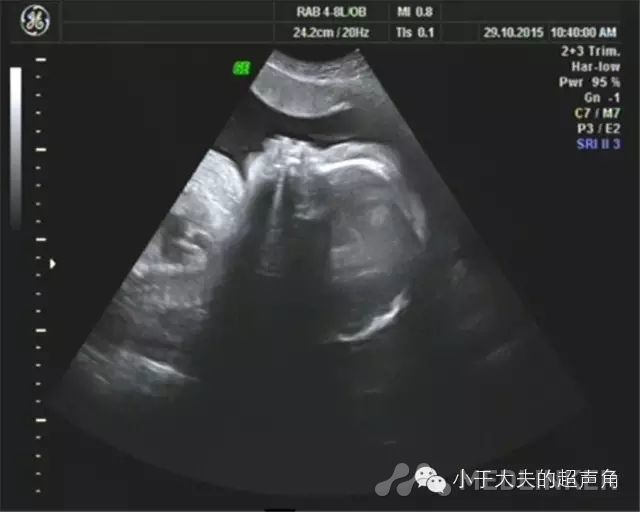

超声表现宫内见两胎儿,其间可见羊膜分隔。A胎儿位于右侧腹,双顶径82mm,头围298mm,腹围338mm,股骨长64mm,体重约2693mm±393g。 胎位:臀位。羊水:最大深度约151mm。CDFI:S/D:4.36,RI:0.77脐带:胎儿颈部未见U型血流。 胎心率:135次/分。大脑中动脉CDFI:S/D:1.78,RI:0.44胎儿腹围明显大于孕周,相当于37W+5天,腹腔内显示液性暗区回声,最宽处约9mm,胎儿心脏扩大,胎儿全身皮下组织增厚,头颅及躯干周围被无回声或低回声区包绕,呈“外套” 样水肿。B胎儿位于左侧腹,双顶径81mm,头 281mm,腹围282mm,股骨长63mm,体重约1914± 279g。胎位:头位。羊水:因右侧腹胎儿挤压,羊水显示不清。CDFI:S/D:3.18,RI:0.69脐带:胎儿颈部未见U型血流。 胎心率:161次/分。两胎儿胎盘:位于前壁,厚约39mm,成熟度:I级。

超声诊断双胎。A胎儿:臀位,孕相当于34周+1胎儿声像图异常改变,心胸比增大,腹腔积液,胎儿皮下水肿,S/D比值增高。(不除双胎输血综合征可能,建议产前咨询及进一步检查)B胎儿:头位,孕相当于32周,胎心偏快4行剖宫产术剖宫产术后确诊为:双胎输血综合征,胎盘中间有很多血管交通支,如下图:图5、双胎输血综合征,可见胎盘中间部分有很多血管相互交织成的血管网 TTTS需鉴别的疾病1、羊水过少&羊水过多:两个羊膜腔内羊水量存在差异并不少见,单凭羊水量差异不足以诊断TTTS。一个胎儿严重的羊水过少或过多,而另一个胎儿羊水正常,应高度怀疑双胎之一孤立性的胎儿异常或胎儿生长受限所致。2、不相称胎儿生长:不相称胎儿生长仅仅是一个征象,简单的是指两胎儿生长明显不同,或不相称胎儿发育异常。TTTS的特征为两个胎儿都经历着病理过程,因此两个胎儿都有异常的超声表现。

双胎输血综合征(TTTs)是指两个胎儿循环之间通过胎盘的血管吻合进行血液输注,导致双胎均出现明显的血流动力学异常,从而引起的一系列病理生理学改变及临床表现。1TTTSの特点①单个胎盘;②两胎儿间伴有纤细分隔隔膜;③两胎儿性别相同;④受血儿羊膜腔内羊水过多,最大羊水池深度>8cm;供血儿羊膜腔内羊水过少,最大羊水池深度<2cm;严重的羊水过少可表现为“贴附儿”;⑤受血儿膀胱增大,供血儿膀胱过小或不充盈;⑥两胎儿生长不对称,体重估测差异>20%;⑦受血儿脐带直径大于供血儿脐带直径; ⑧CDFI:脐动脉舒张末期血流速度减低、消失甚至出现反向血流;静脉导管2a波反向;脐静脉出现搏动血流;⑨胎儿水肿,表现为皮肤水肿、心包积液、胸腔积液及腹腔积液;⑩胎儿超声心动图,受血儿表现不同程度的心力衰竭、心室肥厚、心脏增大。